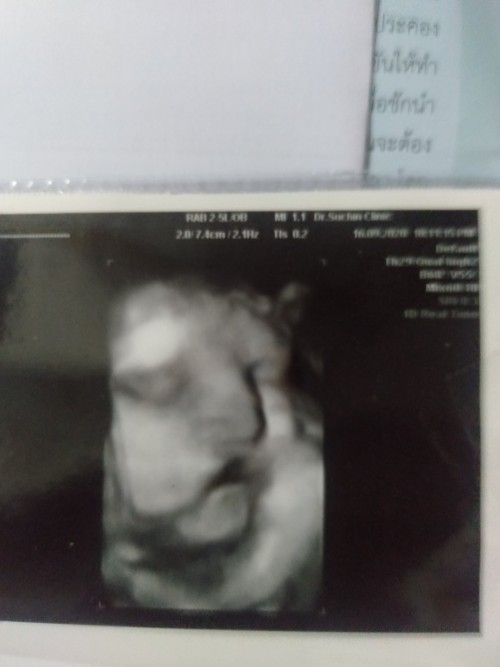

มาอวดรูปตอนซาวด์กันหน่อยค่ะ แม่ๆกำหนดคลอดเดือนไหนบ้างคะ